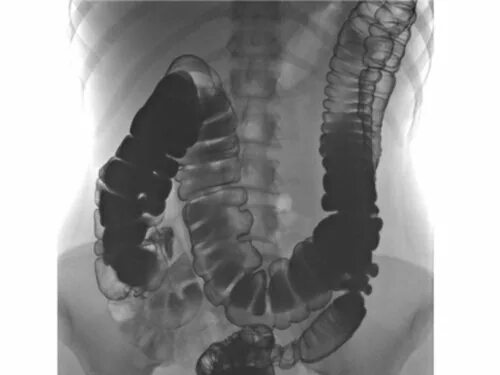

Опущение кишечника симптомы